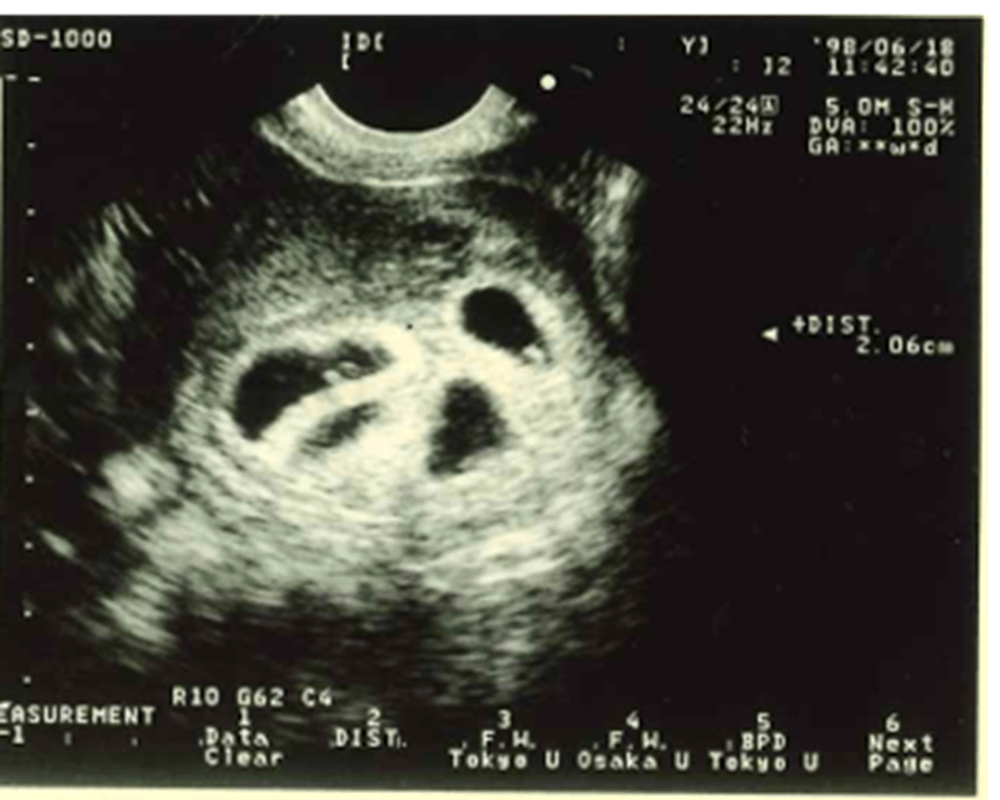

エコー写真(渡邉さんより提供)